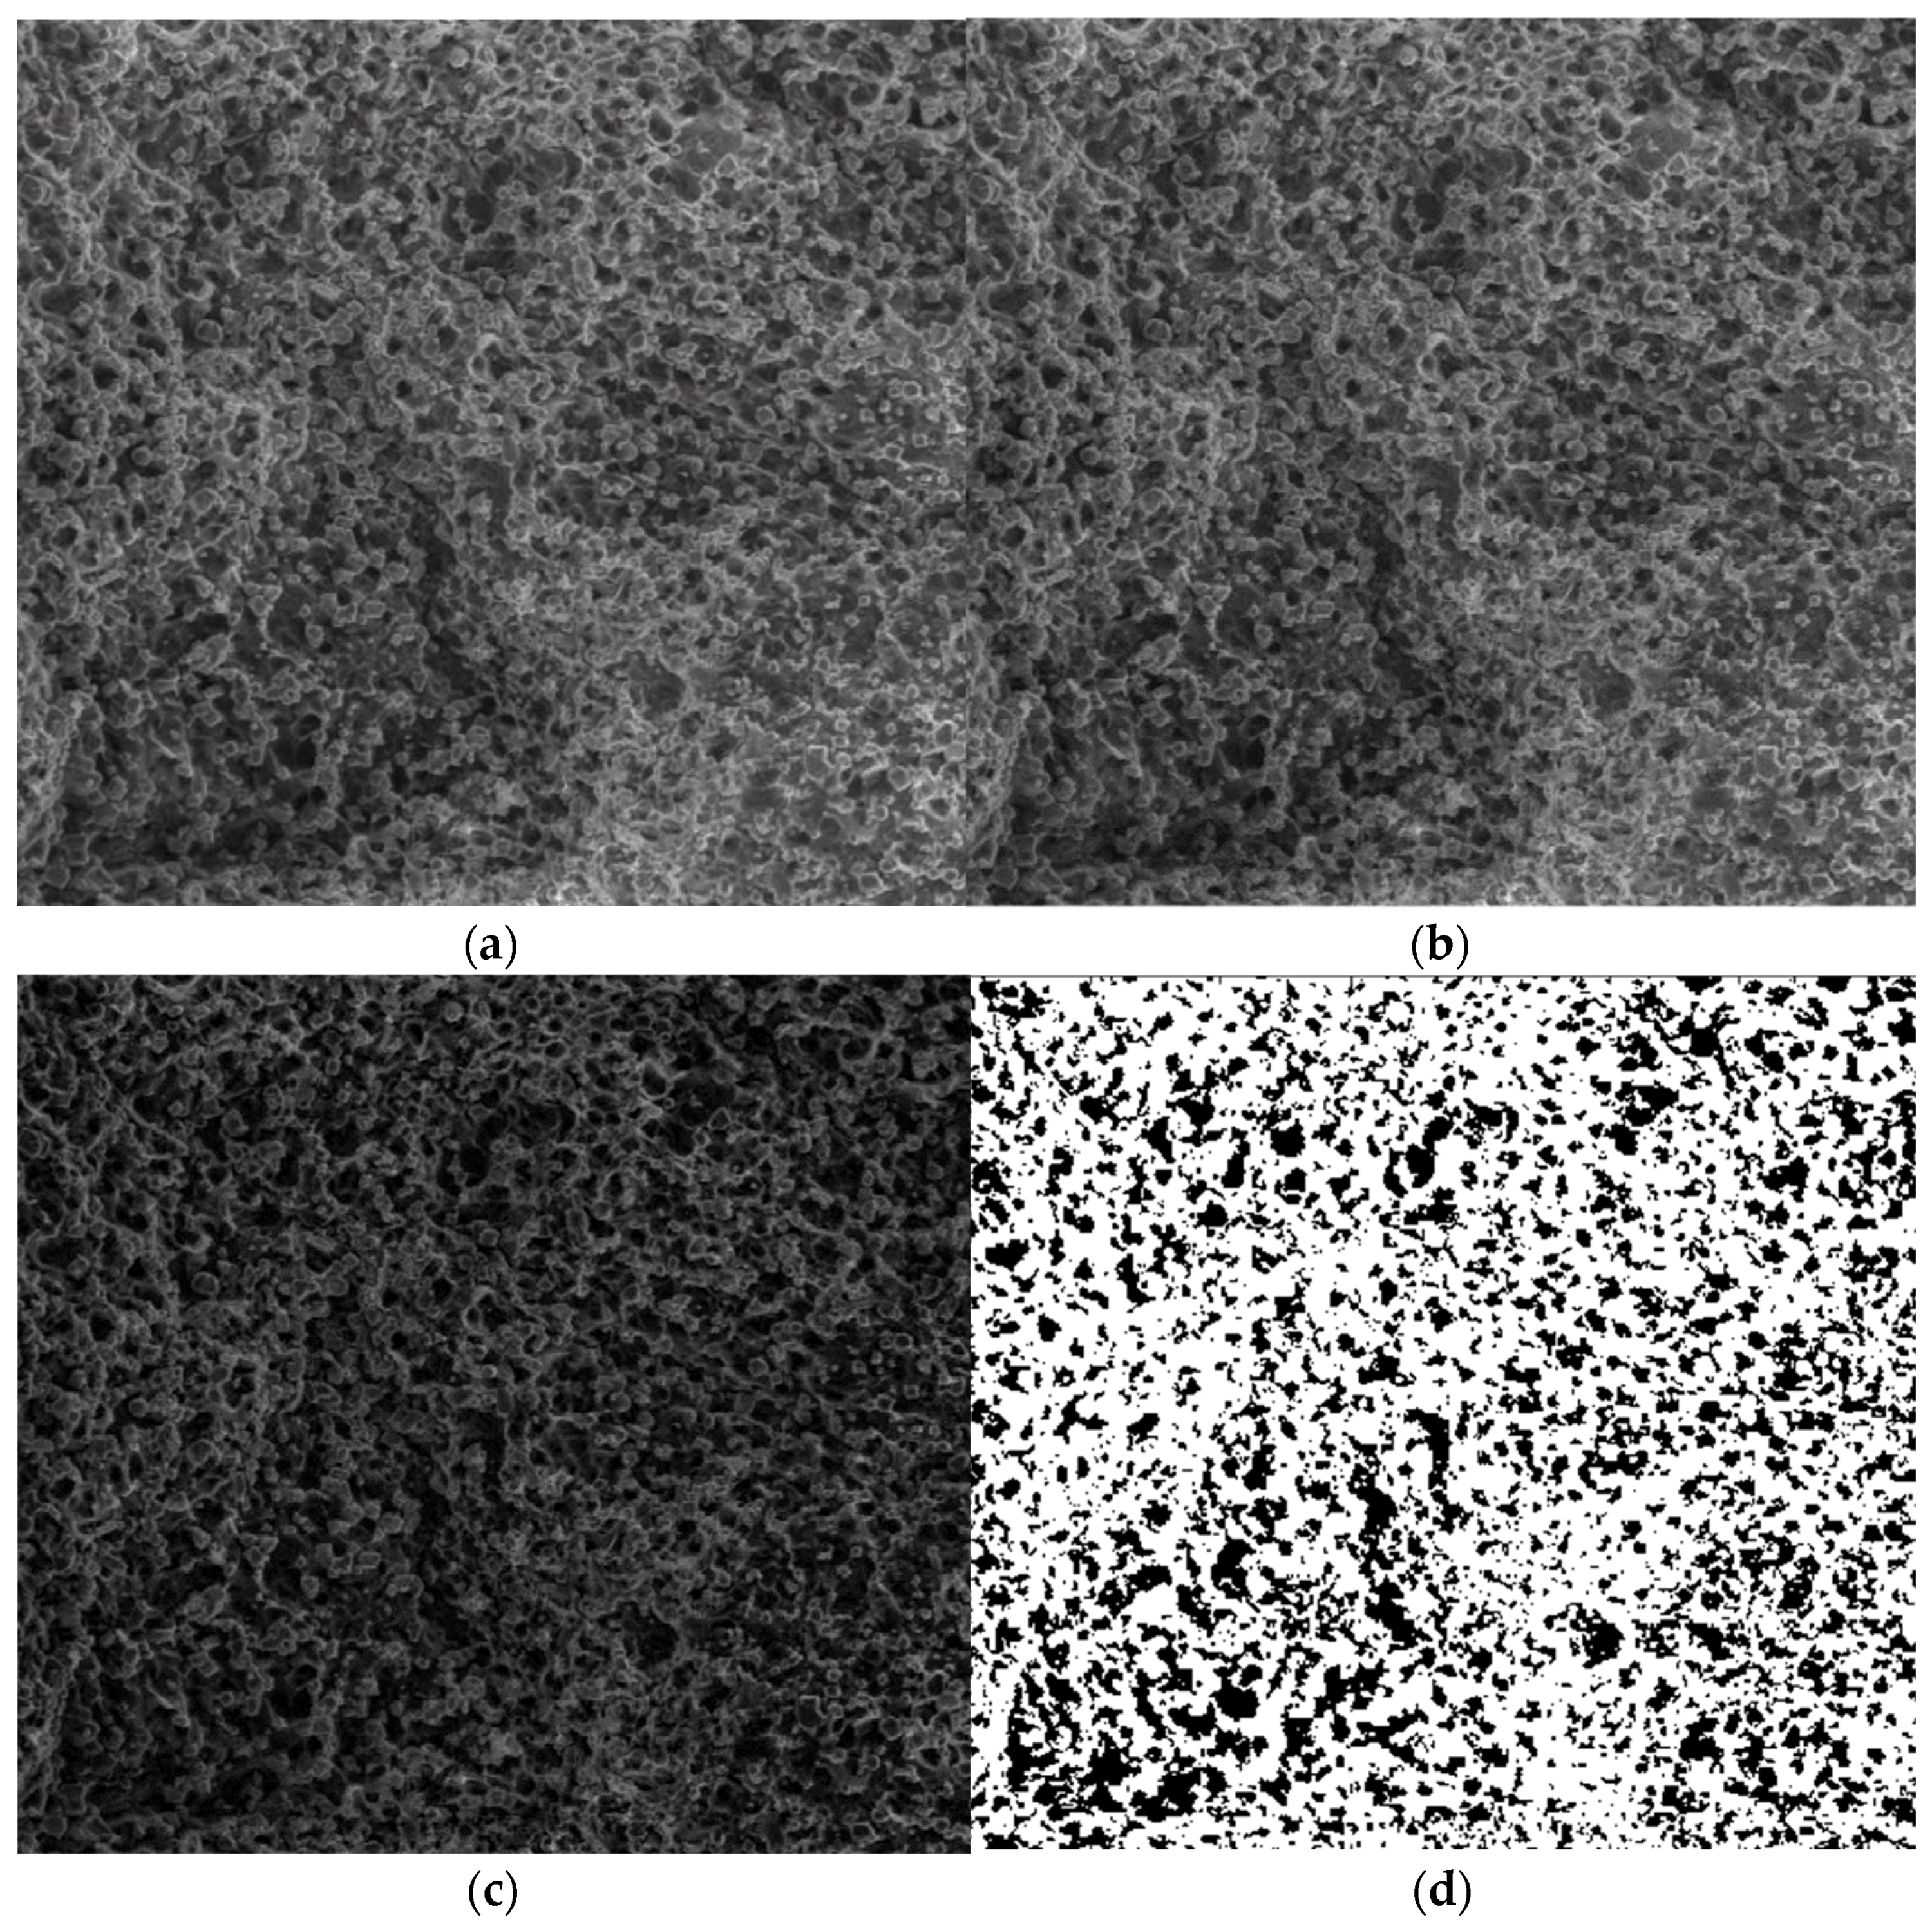

| Name | Fractal Dimension | Standard Deviation | Lacunarity |

|---|---|---|---|

| Image P1 | 1.8621 | 0.0733 | 0.0385 |

| Image P2 | 1.8837 | 0.0894 | 0.0498 |

| Image P3 | 1.8561 | 0.0702 | 0.0324 |